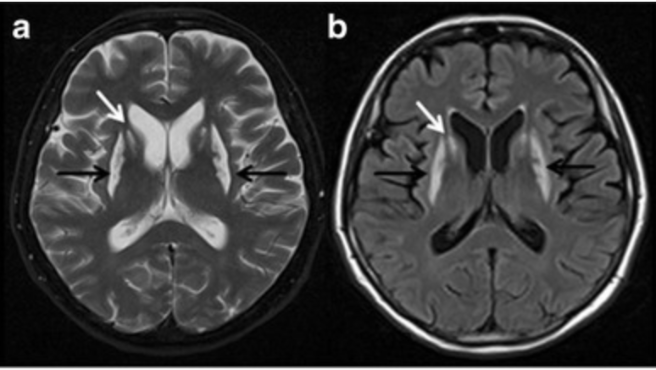

This environmental toxin can cause headache, nausea, vomiting, confusion, focal neurological findings, and the following appearance on neuroimaging.

What is carbon monoxide?